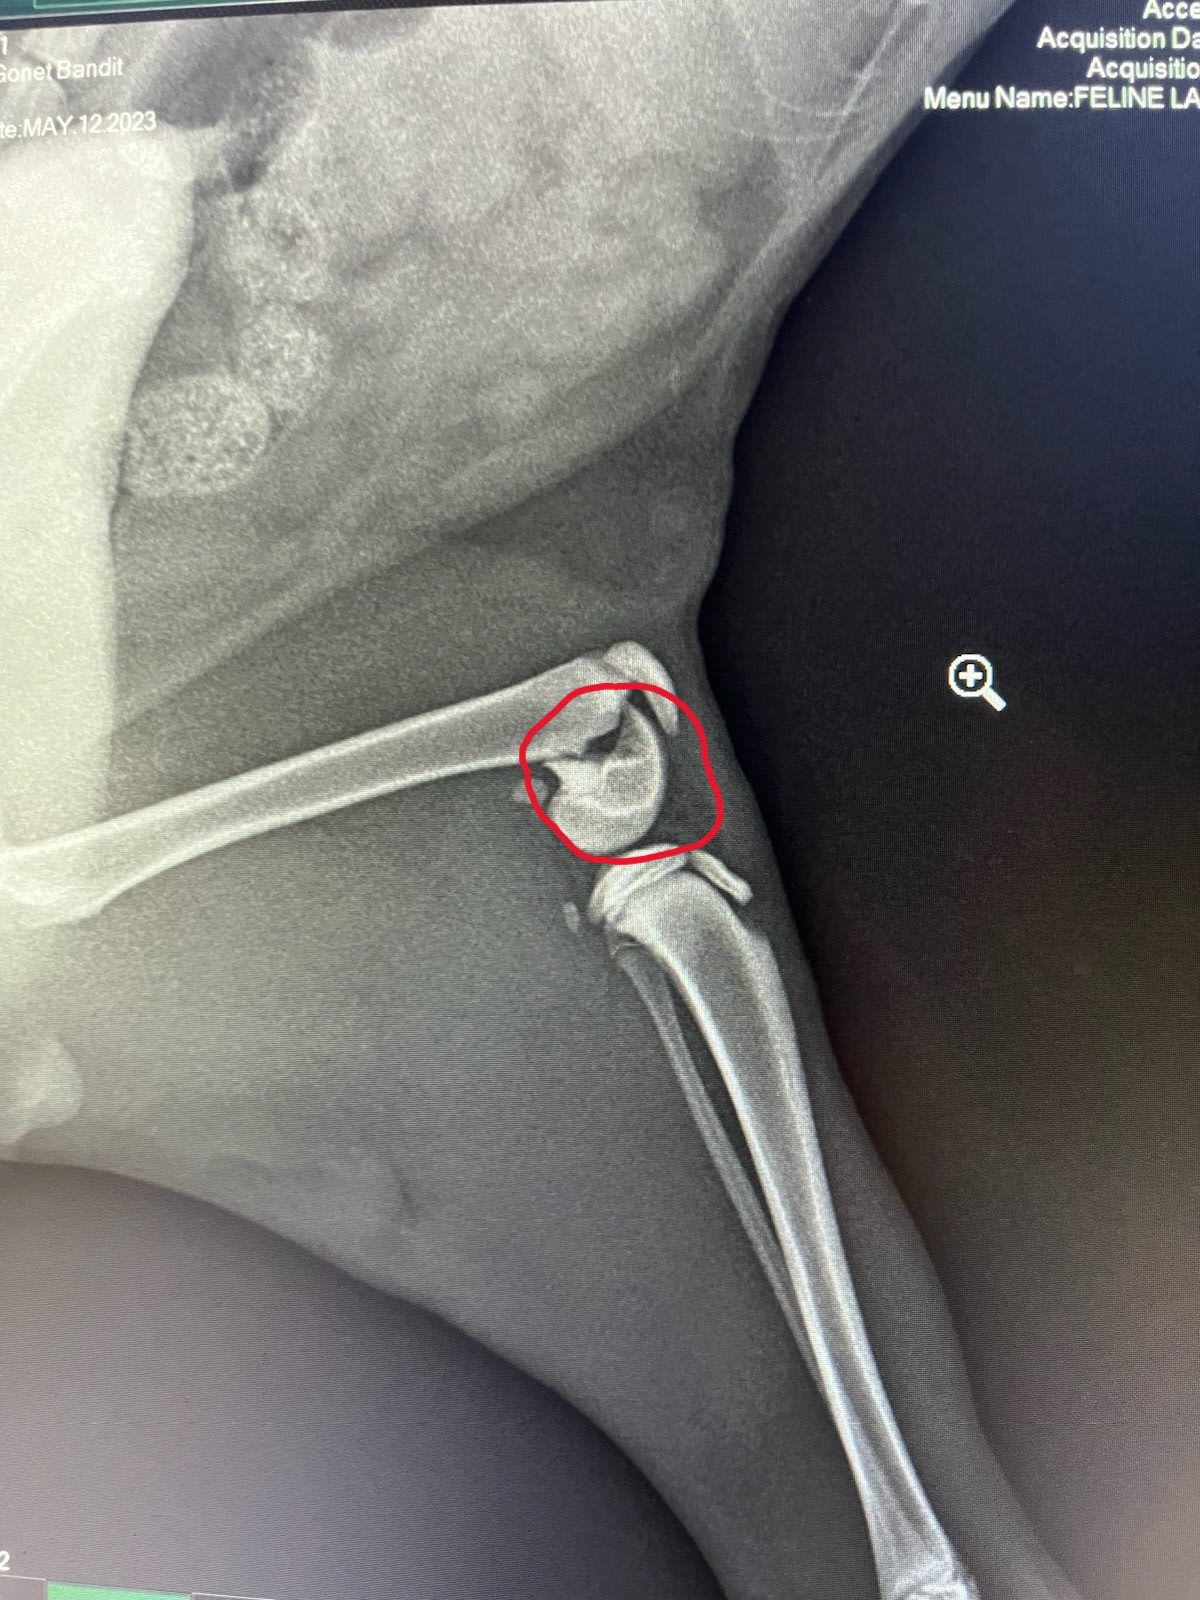

Dropped him at the vet first thing Monday and she contacted me a couple of hours later to tell me he had broken his leg… probably from a fall since there was no evidence of any other trauma… Dammit. Must have fallen from the arbor onto the pavers, or maybe got his leg caught in a fork in a limb on the way down from a tree or something. It’s pretty soft grass under/around the clothes line, so I don’t think that was the culprit.

Here’s a pic of the xray:

As you can see, he broke the distal head of his femur, which the vet said is not that uncommon. Rest and recover (inside) and he will be fine in a few weeks.

He is on pain meds (gabapentin) and something for paristalsis since he was pretty blocked up from not wanting to poop at first. He is getting the hang of it, and took to the litter box fine.

First few days he basically just hung out and slept, then by mid-week he was up and walking around with a limp. Now he is getting more frisky, pouncing on your feet when you walk by, shooting across the floor to beat you to the couch, jumping onto the couch or the sidetable and down again, laying on his back and batting/chewing on the strings that keep the cushions on the dining room chairs, etc. etc. (without any crying or apparent pain).